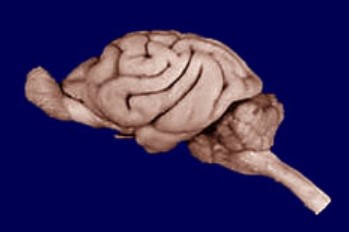

The relationship between basic psychological

processes and underlying functions of the nervous

system. Biological bases of sensation, perception,

motivation, emotion, learning, memory,

psychopathology. Laboratory sections supplement

lectures and readings with practical experience in

neural anatomy, animal (rat) behavioral testing,